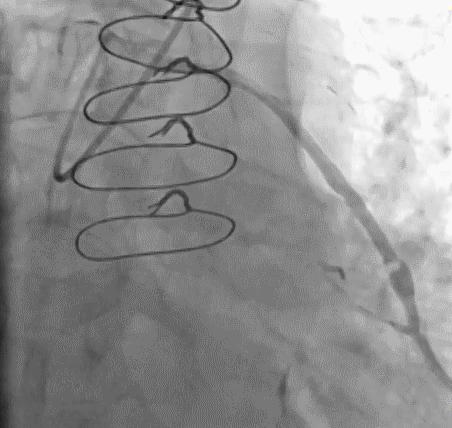

(3)冠状动脉静脉桥血管

首选导管:JR4.0;

其他导管:AL 1.0;AR 1.0

操作:升主动脉造影,寻找静脉桥血管

➢ CASE 3

AL1.0

➢ CASE 4

➢ CASE 5

升主动脉造影未见桥血管显影,原位血管造影也没发现竞争血流迹象,可以确定桥血管已闭塞,必要时可以借助冠脉CTA辅助诊断